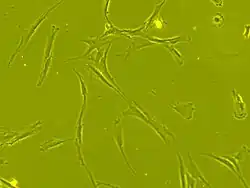

Mesenchymal stem cells (MSCs), a term first used (in 1991) by Arnold Caplan at Case Western Reserve University,[6] are characterized morphologically by a small cell body with long, thin cell processes. While the terms mesenchymal stem cell (MSC) and marrow stromal cell have been used interchangeably for many years, neither term is sufficiently descriptive:

The cell body contains a large, round nucleus with a prominent nucleolus, which is surrounded by finely dispersed chromatin particles, giving the nucleus a clear appearance. The remainder of the cell body contains a small amount of Golgi apparatus, rough endoplasmic reticulum, mitochondria, and polyribosomes. The cells, which are long and thin, are widely dispersed, and the adjacent extracellular matrix is populated by a few reticular fibrils, but is devoid of the other types of collagen fibrils.[13][14] These distinctive morphological features of mesenchymal stem cells can be visualized label-free using live cell imaging.

The International Society for Cellular Therapy (ISCT) has proposed a set of standards to define MSCs. A cell can be classified as an MSC if it shows plastic adherent properties under normal culture conditions and has a fibroblast-like morphology. In fact, some argue that MSCs and fibroblasts are functionally identical.[15]